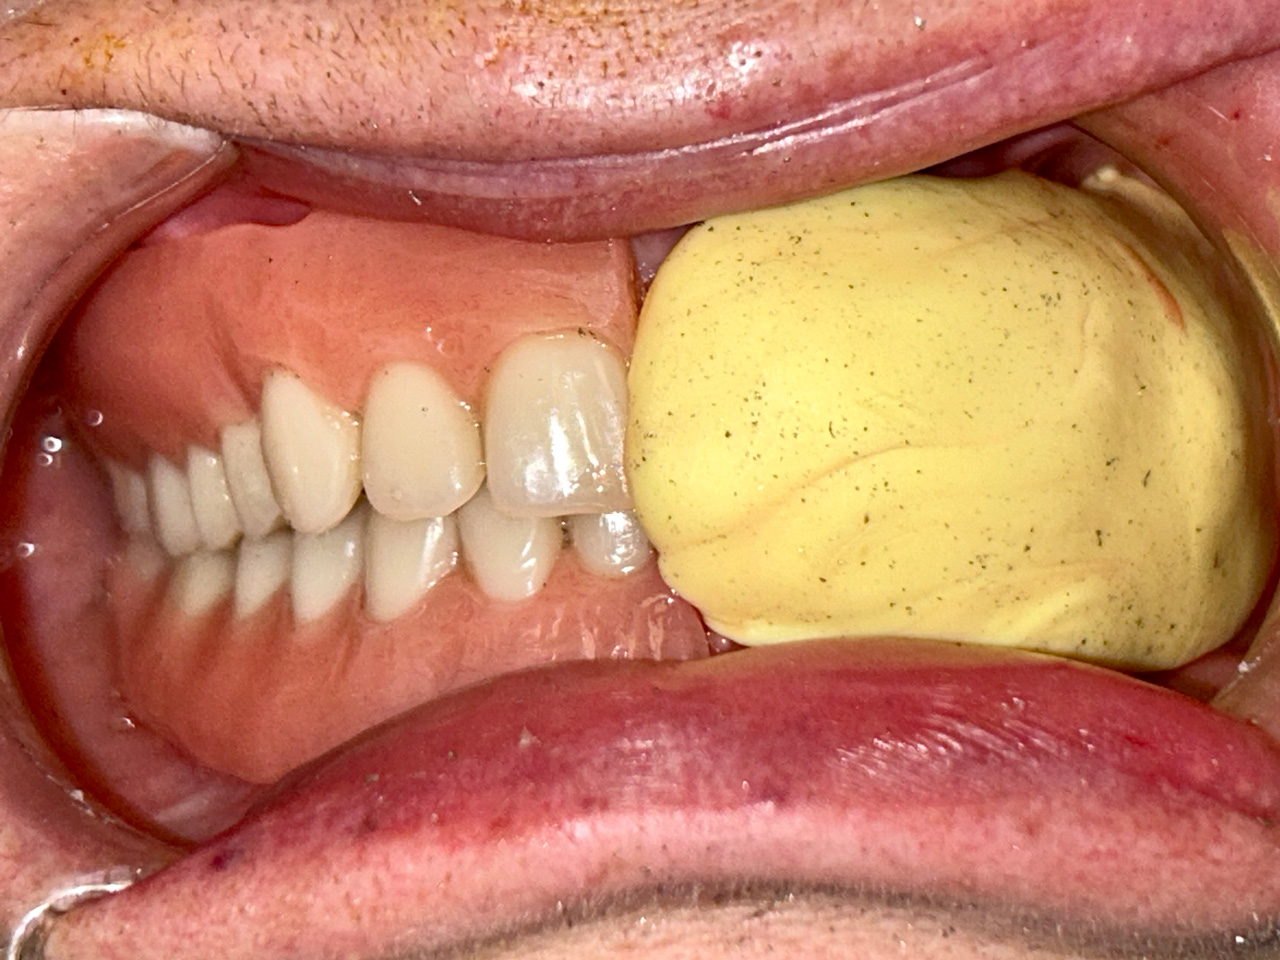

Elhanyagolt fogsor cseréje 2 nap alatt

2 nap alatt varázsoltuk ezt a szép esztétikus alsó, felső körhídat implantátumokkal megtámasztva a korábban elhanyagolt szájba. Az 1. nap 26 fogat távolítottunk el, mert annyira rossz állapotban voltak, és rögtön azonnal terhelhető IHDE svájci implantátumokat raktunk be, fentre 8, lentre 6 darabot. A sebeket összevarrtuk és intraorális szkennerrel digitális lenyomatot vettünk. 2 nap múlva pedig beragasztottuk a kész PMMA műanyag körhidakat. Dr. Kelemen Péter és a Symbion Fogtechnika munkája.